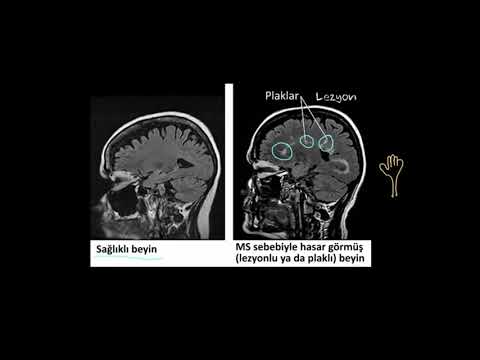

Multipl Skleroz (MS) Nedir?